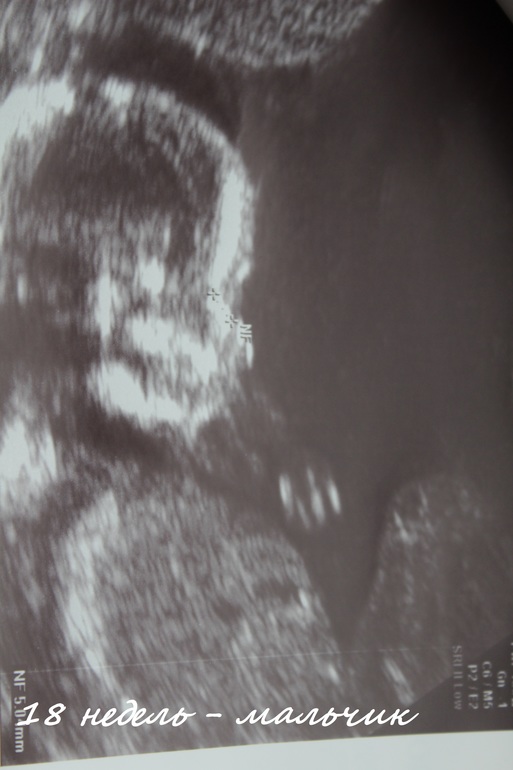

И наша тайна пола раскрыта, у нас будет СЫНОЧЕК!!! Мы очень- очень рады!!!

Вот кто в домике живет